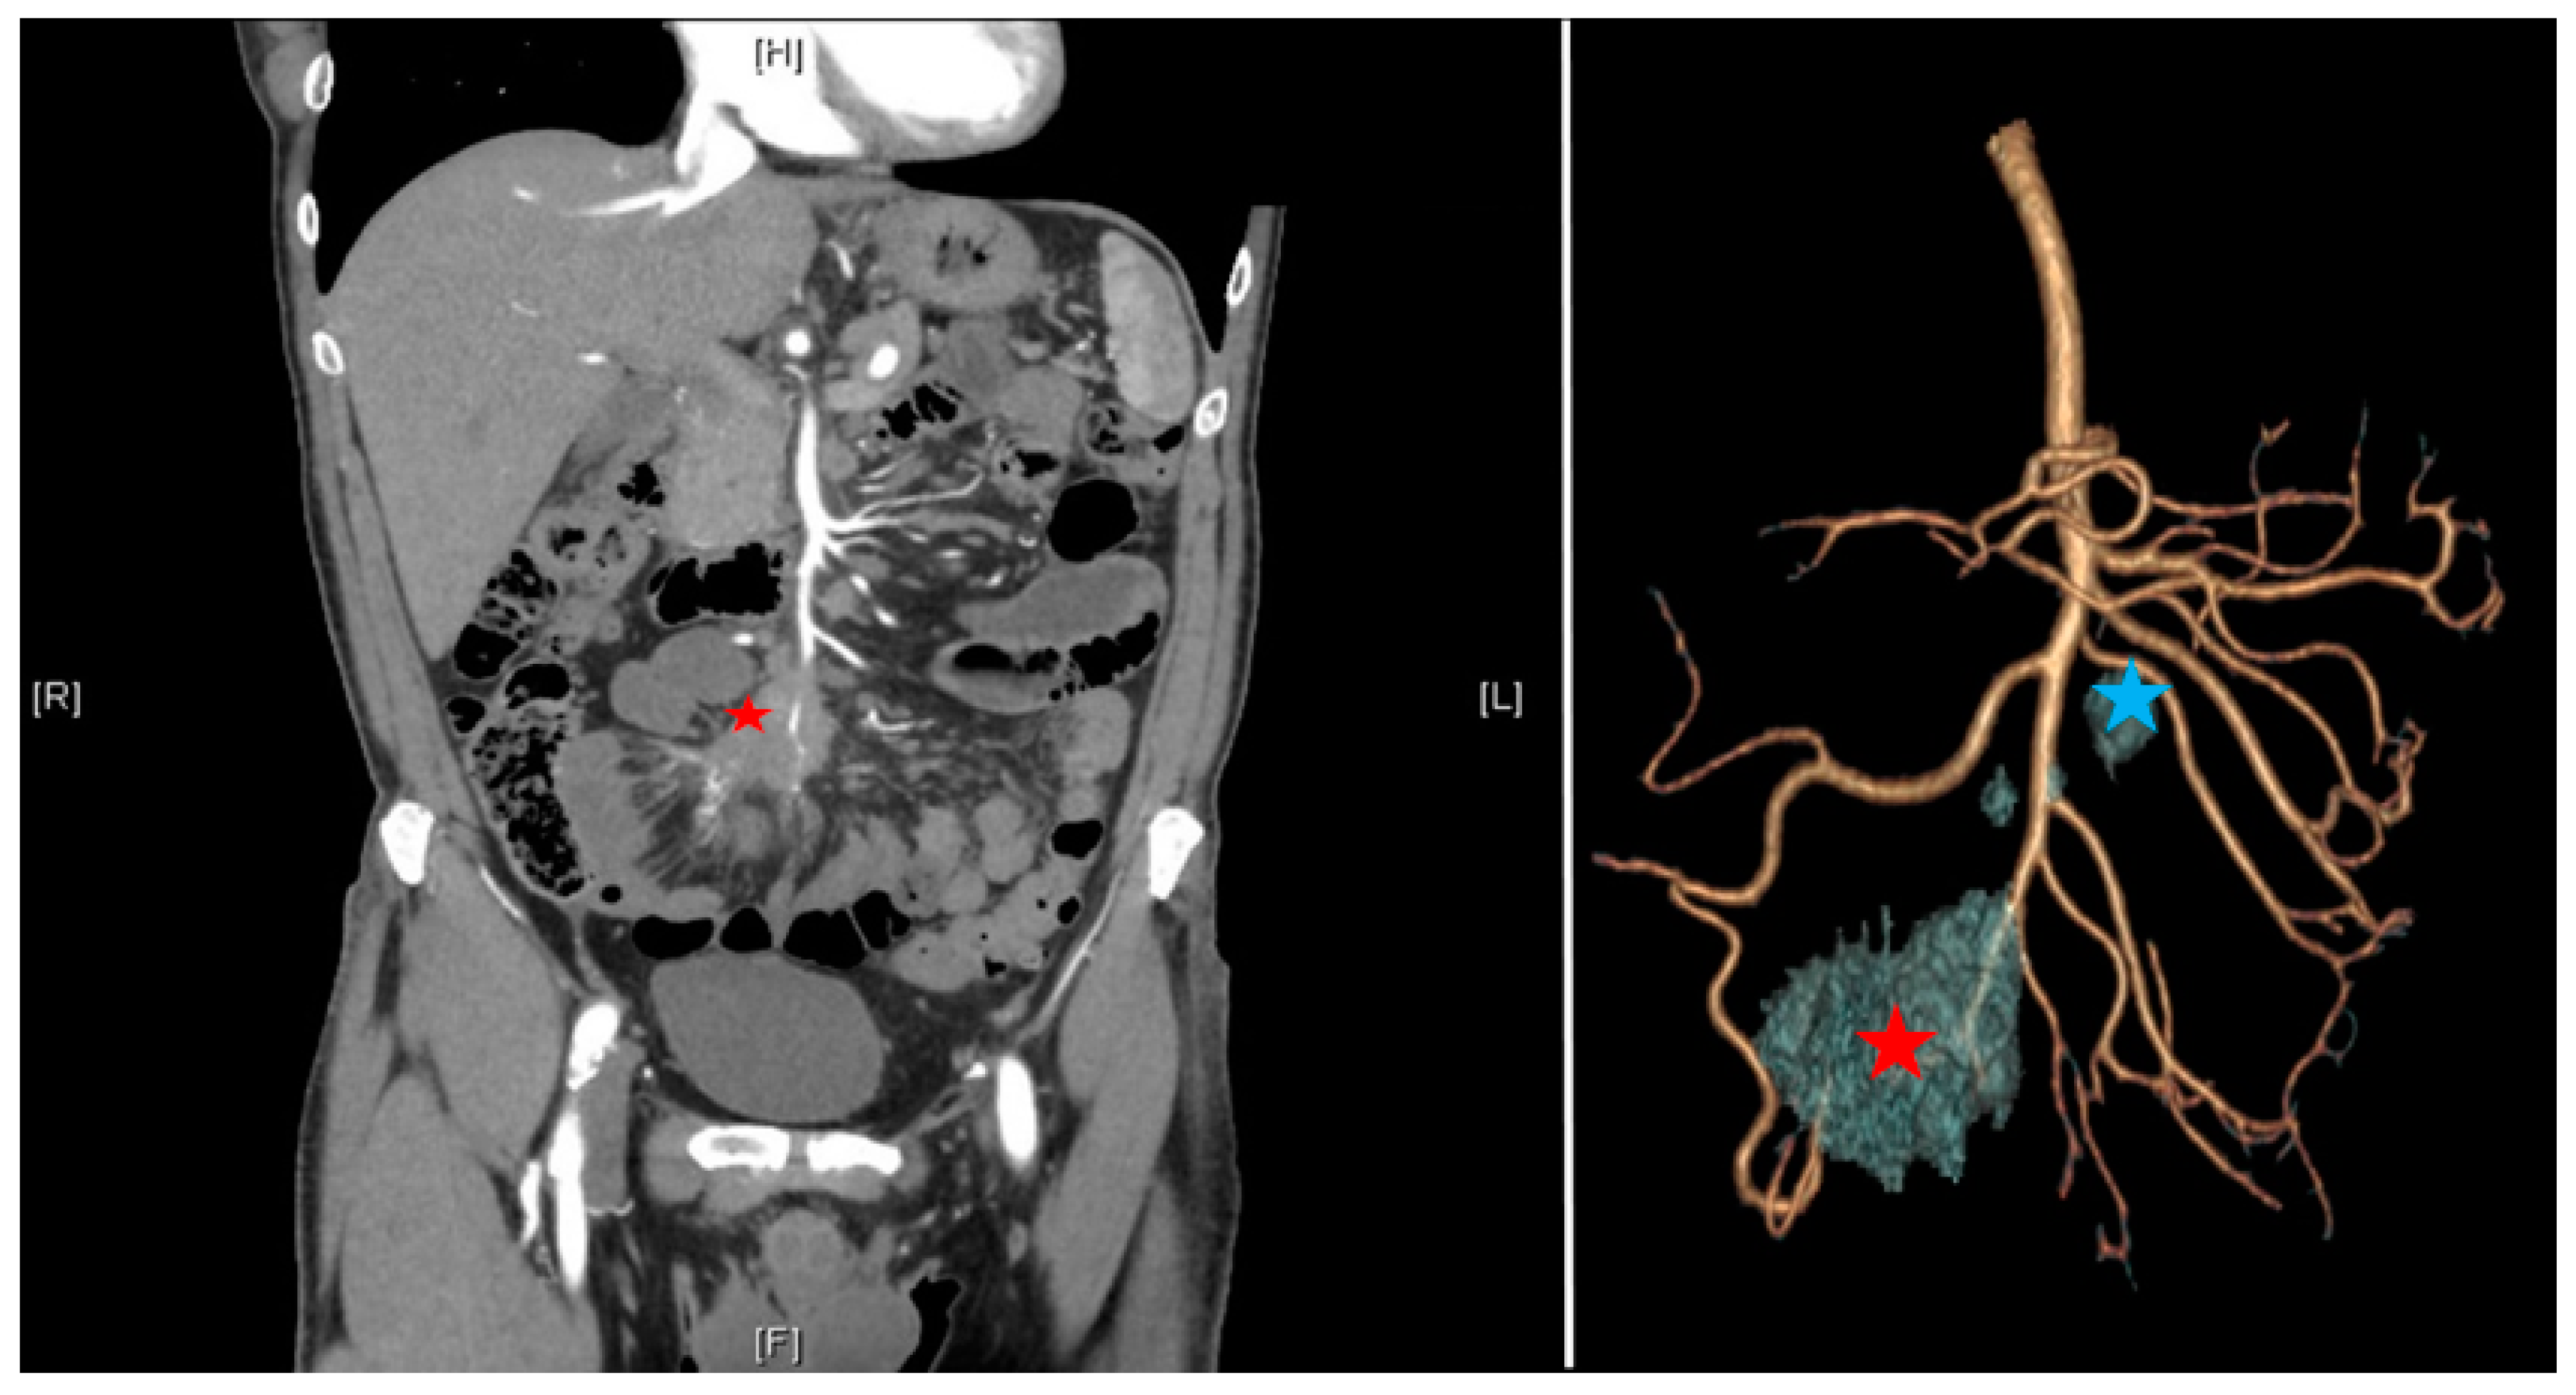

According to the ENETS consensus guidelines [8], the preoperative workout should include a precise evaluation of past medical and surgical history, focusing on the symptoms of carcinoid syndrome (flush, diarrhea, and cardiac failure). Cardiological evaluation should be mandatory to detect tricuspid or pulmonary failure. Morphological evaluation should include a triphasic CT scan including a thin-slice arterial CT angiography (CTA) of the abdomen and pelvis allowing three-dimensional reconstruction to evaluate the vascular involvement [11,12], a PET/CT with 68 Ga (sensitivity of 90%), and a hepatic MRI in cases of suspected metastasis [8]. siNETs are sometimes difficult to see on CT scans, but mesenteric lesions appear as contrast-enhancing and surrounded by striae of desmoplastic reaction. Levels of 24 h urinary 5-hydroxyindoleacetic acid are given but not specific and used only for their prognostic utility. The interest in the three-dimensional reconstruction is multiple: it allows prediction of the extension of the lymph node involvement and anticipation of the resectability according to the Deguelte’s classification [13]. Mesenteric mass invasion is divided into four stages according to its location regarding the superior mesenteric artery (SMA): stage I: proximity to the small intestine; stage II: involvement of the distal branches of the SMA; stage III up: involvement of the trunk of the SMA with <3–4 free jejunal branches; stage III down: >3–4 free jejunal branches; stage IV: involvement of the first jejunal arteries. The limiting component is the number of free jejunal branches allowing a resection without risk of short small bowel syndrome. It is important to standardize the reconstruction technique including arterial and venous vascularization with the mesenteric mass (Figure 2). Patients who are unfit for surgery are the ones presenting peripancreatic vessel involvement (superior mesenteric vein, superior mesenteric artery, coeliac axis, and proper hepatic artery).

Figure 2.

CT scan with arterial three-dimensional reconstruction; mesenteric mass (red star); proximal nodes (group 3 down from Deguelte et al. [13] in blue star).